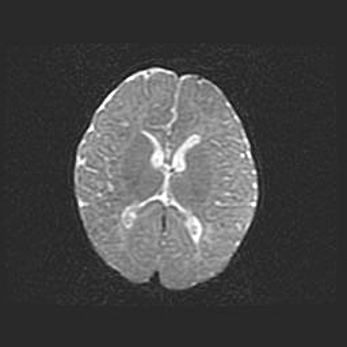

Церебральная ишемия II.

Возраст: 5 дней

Вес: 3400 г

Пол: женский

Окружность головы: 35 см

Срок гестации: 39 недель

Церебральная ишемия – это заболевание, характеризующееся недостаточностью (гипоксией) либо полным прекращением (аноксией) снабжения мозга кислородом по причине закупорки одного или нескольких сосудов. Это приводит к  что метаболическим расстройствам различной степени тяжести в тканях головного мозга, развитию коагуляционных некрозов и гибели нейронов.